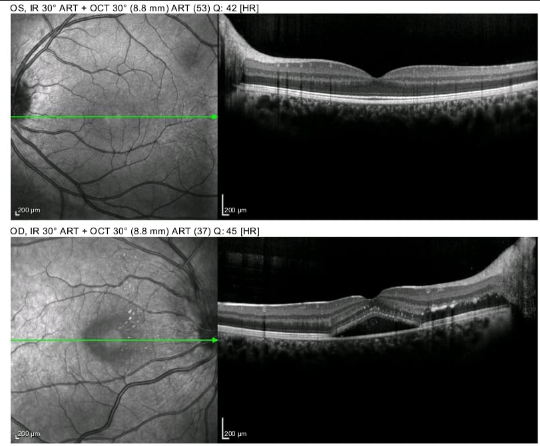

Tomografía de coherencia óptica de segmento anterior, glaucoma y macula, angiografía ocular,  topografía corneal, campos visuales computarizados, ecografía ocular, biometría, microscopia especular.